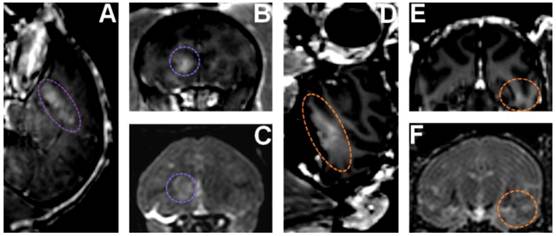

FIGURE 9

In vivo BBB opening in monkeys: (A,B,C) BBB opening experiment targeting the caudate using custom made microbubbles and applying 0.6 MPa (purple dashed line shows region of interest). (D,E,F) BBB opening experiment targeting hippocampus using Definity® microbubbles and applying 0.6 MPa (orange dashed line shows region of interest). (A,B,D,E) 3D Spoiled Gradient-Echo (SPGR) T1-weighted sequence was applied after intravenous (IV) injection of gadodiamide 1 h after sonication. (A,D) Sagittal slices at the region of interest. (B,E) Corresponding coronal slices. (C,F) 3D T2-weighted sequence, an edema was visible using custom made microbubbles while no damage was detected using Definity® microbubbles.